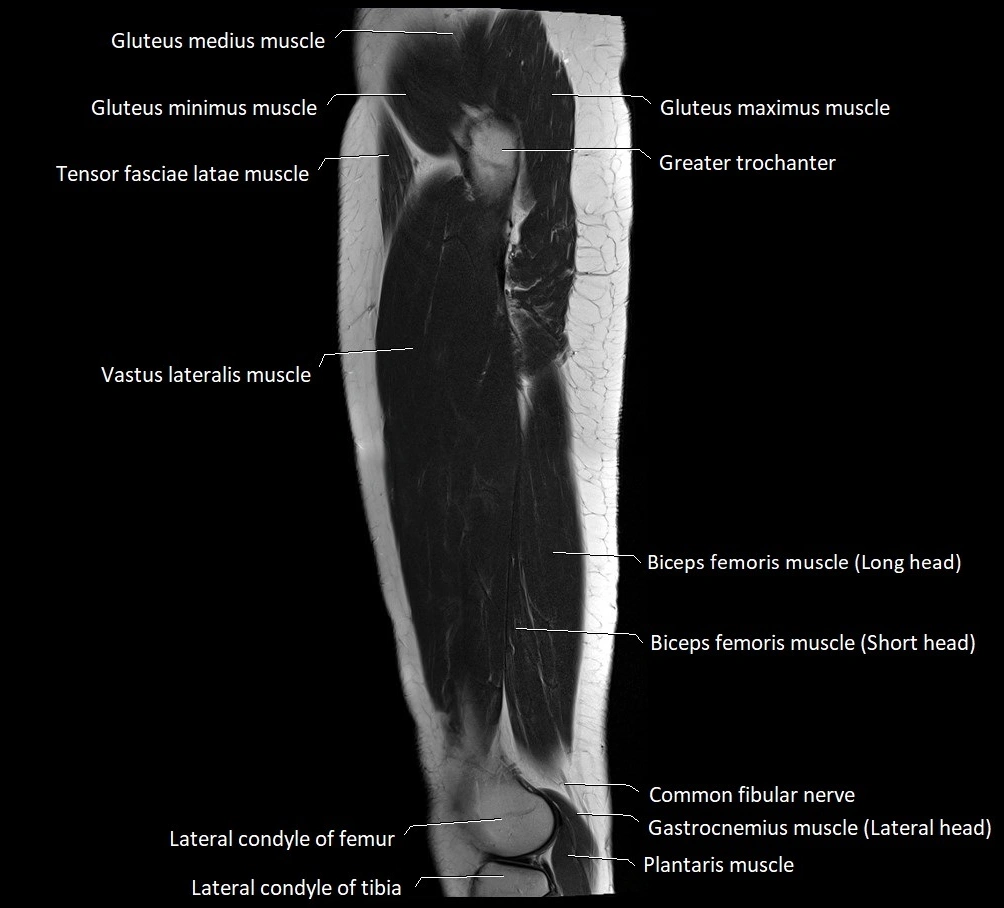

- Biceps femoris muscle (Long head)

- Biceps femoris muscle (Short head)

- Common fibular nerve

- Greater trochanter

- Lateral condyle of femur

- Lateral condyle of tibia

- Lateral head of gastrocnemius muscle

- Plantaris muscle